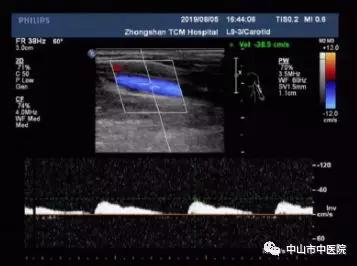

上举体位:上肢动脉频谱血流低速低阻,收缩期时相延长